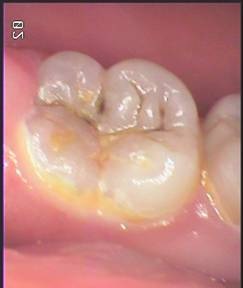

A. 當然是蛀洞越小的時候補越好。當蛀牙洞變大時,因為填補前須把裡面病變的齒質清除,補完之後少數會產生酸痛現象,應該是因為離牙神經過於接近的緣故,一般一段時間酸痛就會消失。如果酸痛一直無法消失甚至越來越明顯對冷熱都有感覺,甚至會出現自發性疼痛,就可能須接受根管治療了。為了避免抽神經,以後還要花錢做假牙或因為沒有錢做假牙導致牙齒因蛀洞太大而被拔掉的機會,當然小小的蛀洞就補起來是最好的選擇。

| Ø 小的蛀牙不補,將來就是大的蛀洞。有哪個人的牙齒一長出來就蛀個大洞的呢?但蛀牙剛形成時「不痛也不癢」,我們怎麼知道自己有蛀牙應該要補?當然是要定期到牙醫診所檢查,才是最省事省時的明確之舉啊! 什麼是齒頸部蛀牙? A. 齒頸部蛀牙好發於中年以後,原因並不明確,但建議若有因刷牙不當造成齒頸部磨損最好儘早處理,避免因琺瑯質破壞,增加齒頸部蛀牙的機會。以下患者因蛀牙深入牙齦下方,所以補牙前要先以電刀去除部分牙齦再行處理蛀牙。但因太晚處理,除去蛀牙後發現牙髓露出須進行根管治療 什麼叫預防性充填? A. 現今牙科觀念特別強調『預防重於治療』,所以在兒童牙科治療上除了『定期檢查及塗氟』外,更積極推動『預防性充填』的重要性。所謂『預防性充填』,就是針對乳臼齒及恆牙臼齒,因為我們認為平滑面不易卡髒東西,但有些孩子的乳臼齒及恆牙臼齒表面的溝紋太複雜了,不易清洗,為避免蛀牙發生所以以溝裂充填劑先將溝紋填平,避免將來更進一步蛀牙的發生。當然沒有一件事是一勞永逸的,所以即便做了『預防性充填』,還是要定時檢查,定時更新。 | |